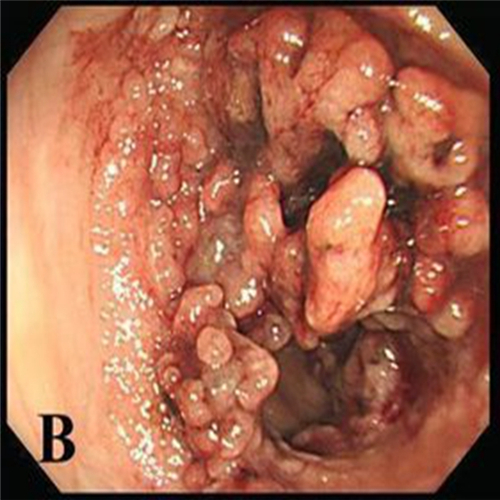

直腸息肉表現

直腸息肉的症狀

直腸息肉早期

直腸息肉脫出的

直腸息肉脫出

直腸息肉糜爛的